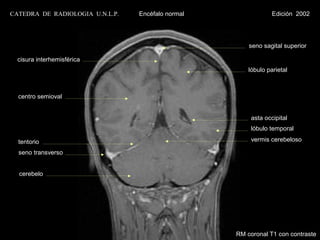

seno sagital superior

cisura interhemisférica

lóbulo parietal

centro semioval

seno recto                                            asta occipital

plexo coroideo

lóbulo temporal

tentorio

seno transverso                                       IV ventrículo

cerebelo

amígdala cerebelosa

RM coronal T1 con contraste